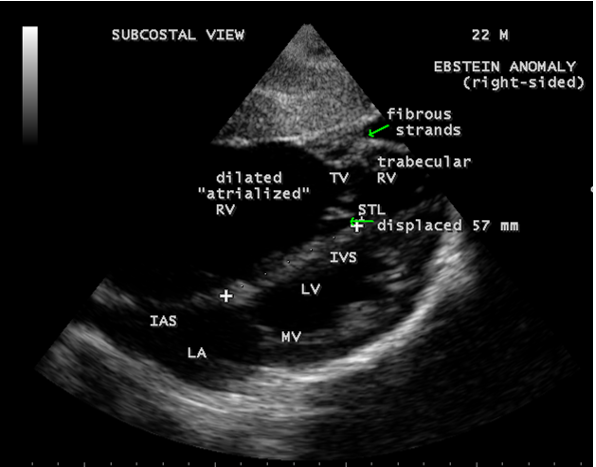

A 22-year old acyanotic male was presented with features of right heart failure and a grade 3/6 systolic murmur at lower left sternal border. 2D echocardiography revealed a normally attached septal tricuspid leaflet (STL), but tethered to the ventricular wall suggesting an Ebstein’s anomaly with severe tricuspid regurgitation swirling around the lateral wall of right atrium and interatrial septum, and a dilated atrium and atrialized RV (right ventricle) as shown in Figures 4 to 8.

Apical displacement always affects the septal leaflet and also involves the posterior leaflet. The leaflets are not displaced beyond the junction between the inlet and trabecular parts of the right ventricle and the point of maximum displacement is usually at the commissure between the two leaflets. The spectrum of leaflet tethering varies from mild to extreme. The degree of dysplasia is also categorized as I to III as shown in Table 4.

When chordae are absent, the free leaflets insert directly into the ventricular wall. In some cases, the greater part of the affected leaflets is firmly adherent to the right ventricular wall, drape the apical trabeculations and completely blended with ventricular wall. The communication between the atrialized and functional right ventricle is confined to slits or perforations in the anterior leaflet as Ebstein originally described. When the anteromedial commissure is fused and the anterior leaflet is intact, the tricuspid orifice is “imperforate” [30] and it occurs in 10% of hearts with Ebstein’s anomaly. In ‘imperforate Ebstein’s anomaly”, the septal, inferior and antero-superior leaflets may fuse either completely or in part, so that the inner surface of the inflow part of the right ventricle is formed by a “blanket” of dysplastic valve tissue towards the apex. The leaflets are said to be “plastered” out of the right ventricular myocardium, so that the fibrous transformation of the leaflets from the muscular precursors remain incomplete. . In severe cases, the leaflets are thickened, focally muscularized and attached to the underlying myocardium by numerous muscular stumps. In extreme cases, the fusion of leaflet tissue is so complete as a membrane-like continuum and the only identified remnants of leaflet tissue are nodular fibrous ridges at the level of the displaced functional annulus. In this setting, the entire inflow tract is atrialized and the functional right ventricle consists only of trabecular and outflow (infundibulum) components. The designation of “atretic“ Ebstein’s malformation was documented by Kumar [31] to the imperforate fused tricuspid valve and its incidence becomes even higher to 29% with an inclusion of “pinhole” communication {32}.

Echocardiographic features Echocardiography is the diagnostic test of choice for Ebstein’s anomaly and the first echocardiographic diagnosis was reported by Lundstrom in 1969. The first diagnostic criteria for Ebstein’s anomaly using a multi-crystal two-dimensional system was defined by Hagan in 1974 [33] and they were able to recognize the apical displacement of the septal tricuspid leaflet and an elongated anterior tricuspid leaflet with increased excursion. The septal leaflet of the tricuspid valve attaches chiefly to the ventricular septum , but part of its basal attachment is to the posterior wall of the right ventricle [34] and it normally exhibits a slight but distinct apical displacement of its basal attachment to the central fibrous body compared to the mitral valve. The distal displacement of septal origin of tricuspid valve seems to be the best echocardiographic criterion as the characteristic sign for Ebstein’s anomaly and the degree of maximal displacement in normal hearts varies considerably with a mean difference of approximately 6 mm with mitral valve. To define the anatomic severity of Ebstein’s anomaly, four-chamber view is the best to demonstrate the apical displacement of septal tricuspid leaflet [35]. The ratio between the mitral-to-apex distance and the tricuspid-to-apex distance varies from 1 to 1.2 in normal subjects and 1.8 to 3.2 in patients and it is 3.6 as in Figure 18 with Ebstein’s anomaly. The true distance in the level of insertion of atrioventricular valves is obtained by substracting the tricuspid-to-apex distance from the mitral-to-apex distance with a mean value of 27.25 ± 12 mm in patients with proven Ebstein’s anomaly and it is 60 mm as shown in Figure 18 compared to reference group (5.7 ± 2 mm). Kambe and coworkers calculated the distance between both atrioventricular valves directly as a mean value of 21 mm with a range of 14 to 32 mm [36]. A maximum difference in the level of valve insertion of >15 mm in children and >20 mm in adults is discriminated between normal and Ebstein’s anomaly [37],[38]. Despite this fact, a patient with an ‘unequivocal’ Ebstein’s malformation can be encountered in whom the diagnosis cannot be made with certainity solely on the basis of apical displacement of the septal tricuspid valve leaflet. Occasionally, the leaflet attaches to the trabecular part rather than the inlet part of the septum, the conventional four-chamber view will not reveal any septal insertion as shown in Figures 28 and 29.